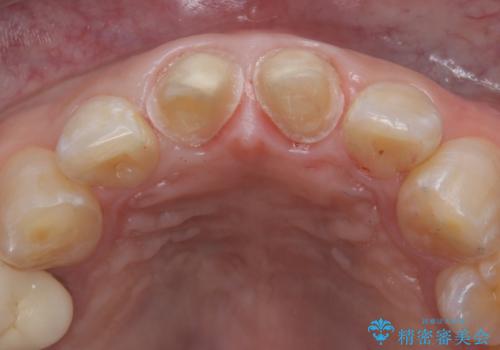

前歯の根のところに違和感がある|根尖性歯周炎|精密根管治療|オールセラミッククラウン|見た目も改善

- 前歯の違和感を主訴にご来院された患者様です。

根尖性歯周炎に罹患し根の先に膿が溜まっているのが原因でした。

精密根管治療後、オールセラミッククラウンで治療を行いました。

精密根管治療では、菌を入れない環境を作り見逃しが無いようにマイクロスコープを使って治療する事が大切です。

まだ誰も触っていない根管ならばほとんどのケースで治せる事が出来ます。